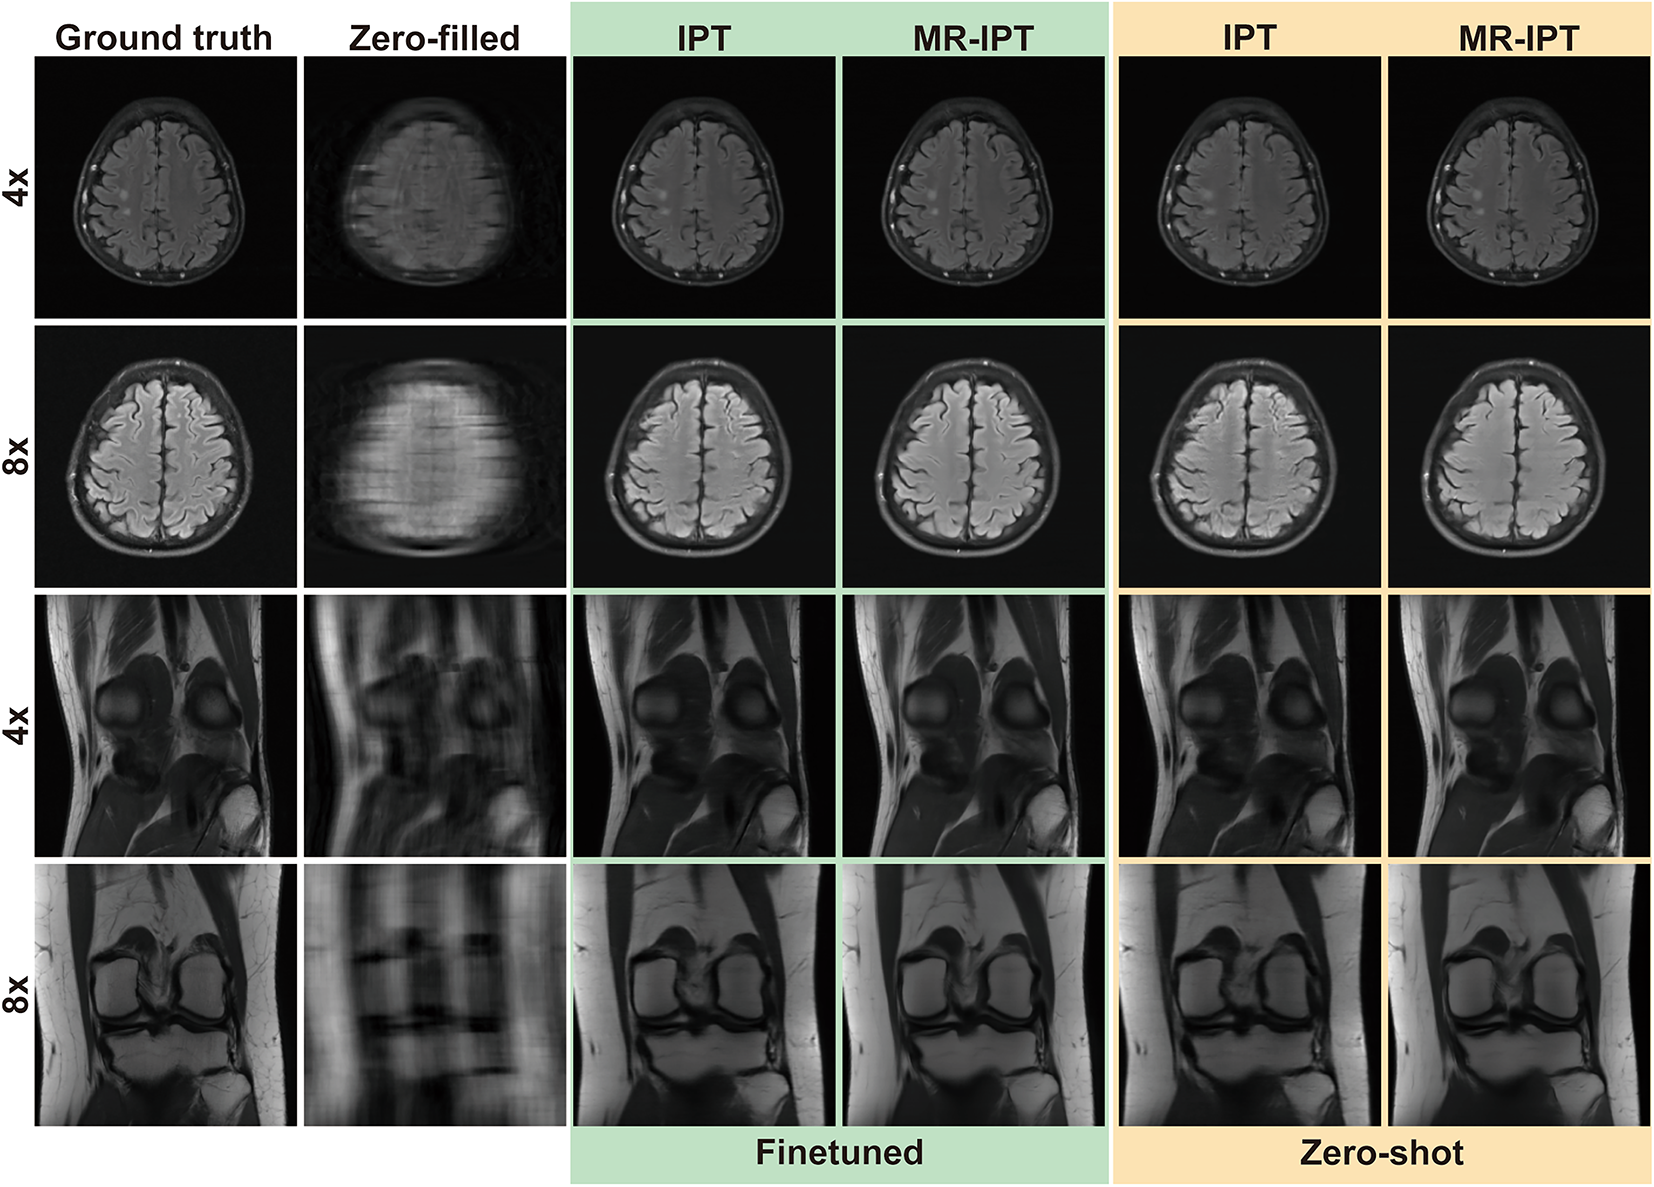

Comparison of MR-IPT and IPT restorations across different undersampling settings. This figure evaluates the performance of MR-IPT against the original Image Processing Transformer (IPT) under both fine-tuned and zero-shot scenarios. Results in the green block represent fine-tuned comparisons, where both IPT and MR-IPT were trained on 4× and 8× undersampling with Cartesian random and Cartesian equispaced masks. Results in the yellow block illustrate zero-shot comparisons, where models were tested without additional fine-tuning. The results demonstrate that MR-IPT consistently outperforms IPT, achieving higher restoration fidelity, better structural preservation, and reduced artifacts, highlighting its superior adaptability and generalization capabilities.